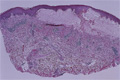

• š(2)Vesiculobullous disease (Pemphigus vulgaris)

Macroscopic image: Bullous pemphigoid commonly occurs in or after the 7th decade. Tense bullae with erythema are seen. This disease is sometimes associated with visceral malignancy.